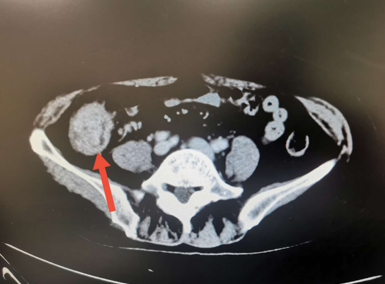

回盲部病变

回盲部占位或炎症的影像鉴别诊断